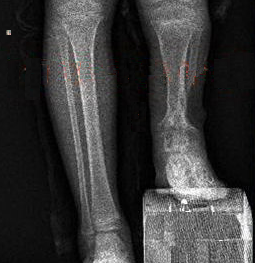

入院检查,患儿站立时,左脚掌根本无法接触地面,左腿跛足,步态异常。文根主任带领团队会诊,共同研讨治疗方案,通过详细分析病情,决定行胫骨近端截骨延长术,Ilizarov外固定器固定。

由于周密的术前准备,手术过程非常顺利,术后小王需要每天旋转外固定架上的齿轮,每天将肢体延长1毫米。一旦牵拉过度,不仅影响骨膜成骨,还可能导致神经受损,引起神经功能障碍,甚至瘫痪。

经过近两个月“延伸”后,小王终于拥有了两条等长的腿。在文根主任指导下,积极康复锻炼,三个月后新生骨矿化,拆除外固定器,效果非常好,如今已经像正常人一样自如行走。

首先在胫骨近端截骨,保留骨膜的完整性。然后在外固定架的辅助下,缓缓牵引,骨膜会随同牵长,骨膜受到刺激,骨膜上的成骨细胞增殖,生成新骨。随着骨骼的牵引,新生骨膜越来越长,牵长的骨膜会长出很多新骨,从而达到骨延长的目的。

临床上一般采用1mm/天的牵引策略,既能保证骨膜不被牵引力撕裂,同时又不会因为牵引太慢导致提前骨化。术后患者应避免剧烈运动,减少患肢活动量,日常注意锻炼下肢肌肉力量,练习肌肉的收缩有助于起支撑作用。